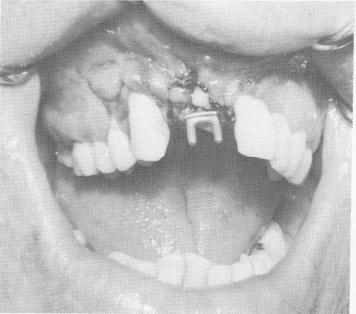

Fig. 12-95. After 3 weeks the tissue around the implant was completely healed.

Fig. 12-96. A two-unit acrylic splint was cemented over the protruding posts.